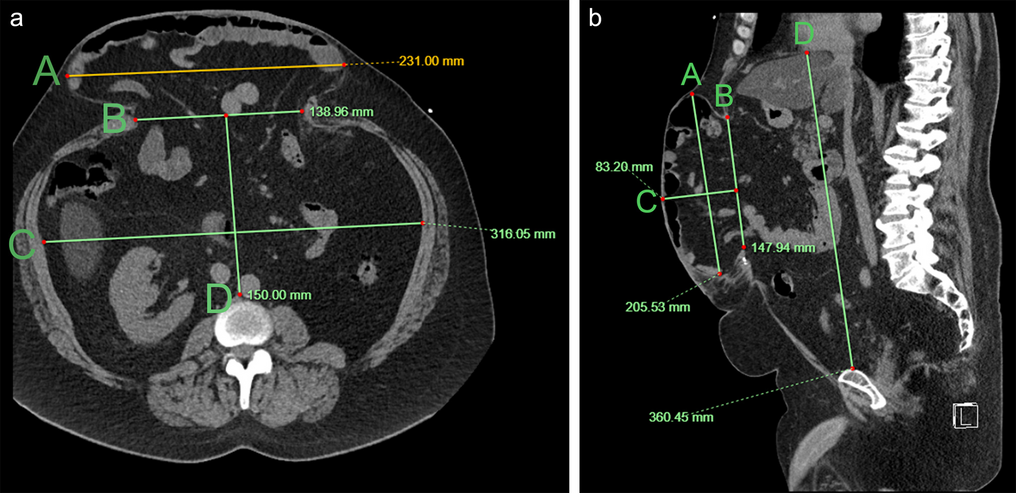

Hernia and abdominal cavity dimensions were measured on the pre-surgical imaging (CT or MRI) according to the method suggested by Tanaka et al. [15] (Fig. 3). Hernia and abdominal cavity volumes were calculated using the formula for ellipsoid shapes, also suggested by the same group: \(Volume=\frac{4}{3}\times \pi \times (length \times width\times height)\). All measurements were performed by a trained interventional radiology resident (DG).

Fig. 3

Non-contrast-enhanced abdominal computed tomography denoting measurements of abdominal and hernia cavities dimensions in axial (a) and sagittal (b) projections. On the axial projection (a), line A denotes the widest axial diameter of the hernia sac, line B is measured at the hernia neck, and lines C and D denote the widest transverse and anteroposterior abdominal cavity dimensions, respectively. On the sagittal projection (b), line A denotes the widest craniocaudal dimension of the hernia sac, line B denotes the widest craniocaudal dimension of the hernia neck, line C denotes the widest anteroposterior dimension of the hernia sac, and line D is measuring the widest craniocaudal dimension of the abdominal cavity from the diaphragm to the superior aspect of the pubis